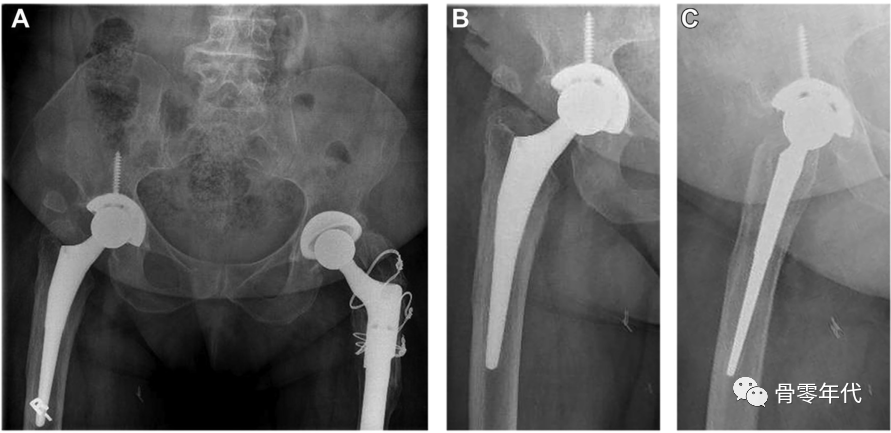

(A-C)术前X光显示左侧股骨近端骨量减少,翻修时预先放置的模块化骨干接合股骨柄用于假体周围骨折的治疗。(D和E)在外展肌重建前进行的MRI图像显示臀中肌和小肌脂肪萎缩,股骨肌腱附着处改变。(F和G)外展肌重建18个月后的部分MRI图像显示臀中肌附着完整,臀小肌部分连续。患者报告的外展肌重建术23个月的结果包括:静息疼痛,1/10;行走疼痛,3/10;Harris髋关节评分,61;牛津髋关节评分,22。患者报告中度跛行,仅需长时间步行时需要拐杖。

病例2:一位60岁女性主诉右髋部疼痛和外展肌无力,在初次右全髋关节置换术后出现大转子骨折。2/5 外展肌肌力。

(A-C)术前X光显示大转子有轻微骨折,和先前植入的右全髋关节假体,包括非骨水泥的股骨柄和非骨水泥的髋臼假体。(D和E)在外展肌重建前进行的MRI图像显示臀中肌腱仍然附着在大转子骨折片段上。这块骨折碎片已经移位,近端移位。臀小肌腱终止于股骨近端的软组织。外展肌重建术后18个月的报告包括:休息疼痛,3/10;行走疼痛,8/10;Harris髋关节评分,26;牛津髋关节评分,37。患者报告中度跛行,行走时使用助行器。

病例3:1例81岁女性患者,左外侧髋部和腹股沟疼痛。在初次全髋关节置换术前,体检记录为Trendelenburg步态和4/5的外展肌力。MRI显示肌腱病变和累及臀中肌和臀小肌腱的部分撕裂的征象。在初次全髋关节置换术中,在股骨近端的止点发现了臀中肌和臀小肌腱部分撕裂。全髋关节假体植入后,一期缝合修复。手术后,她恢复得很好,但最终在大转子上出现了越来越多的疼痛。检查中发现3-4/5外展肌力。手术切除异位骨化。外展肌经经骨隧道进行部分修复,并通过臀大肌和阔筋膜张肌的转移来加强修复。

(A-C)术前X光显示先前植入的右侧全髋关节假体,包括非骨水泥的股骨柄和非骨水泥的髋臼假体。(D和E)外展肌重建后12个月MRI图像显示臀中肌、臀小肌、臀大重建瓣和阔筋膜张肌重建瓣完整。患者报告的外展肌重建术22个月的结果包括:静息疼痛,1/10;行走疼痛,3/10;Harris髋关节评分,58;牛津髋关节评分,23。病人报告说,走路时有轻微的跛行和拐杖。